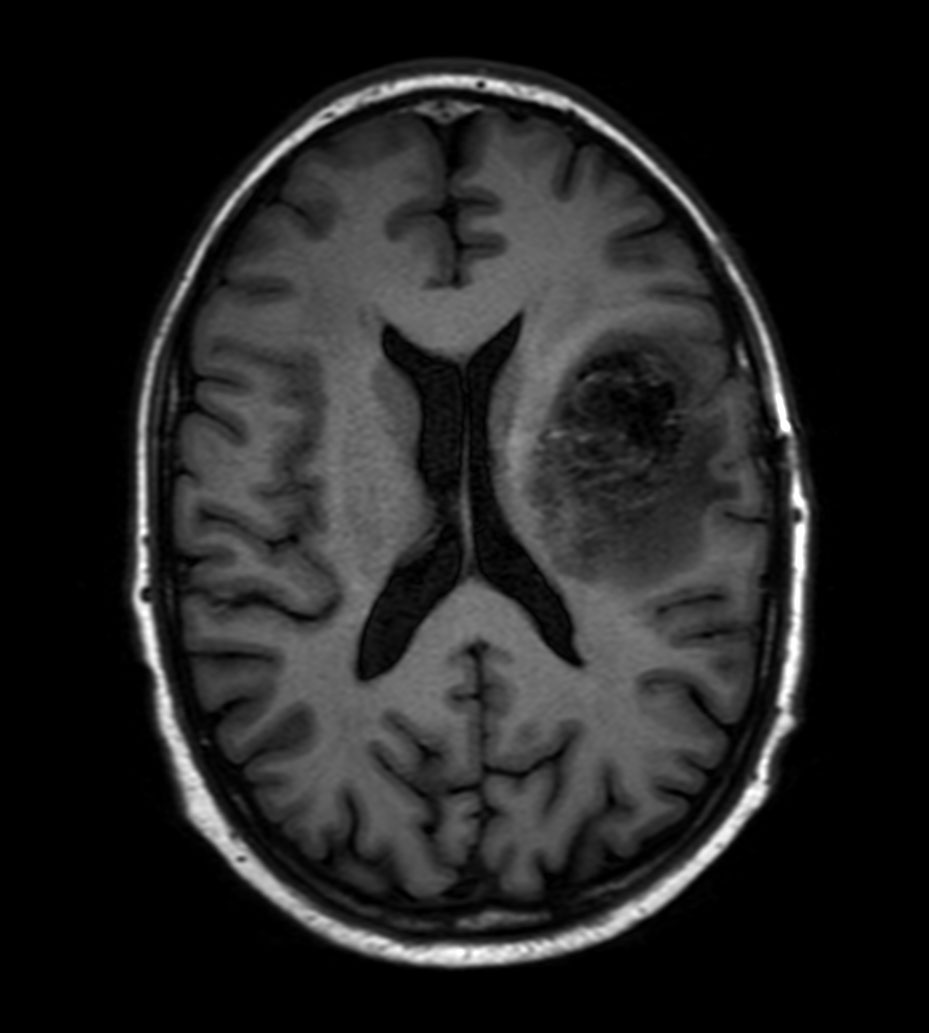

Axial T1w IR TSE